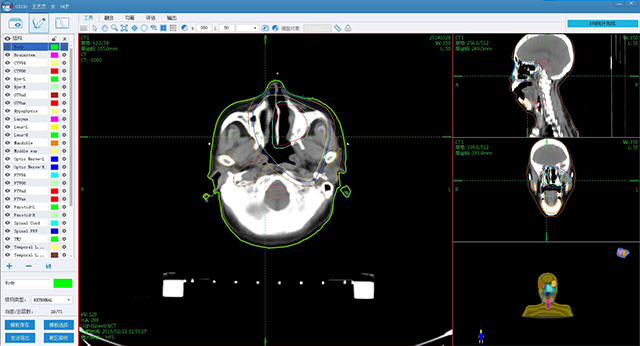

è‚؟çک¤و”¾ç–—ن؟،وپ¯هŒ–ن؛§ه“پ

ه®‰è¯؛ن؛‘و™؛è؟œç¨‹و”¾ç–—هچڈن½œه¹³هڈ°

è‚؟çک¤و™؛و…§هŒ»ç–—